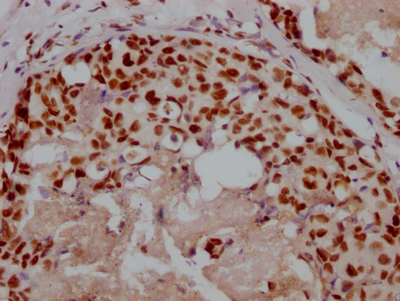

IHC image of CSB-RA555705A0HU diluted at 1:100 and staining in paraffin-embedded human skin tissue performed on a Leica BondTM system. After dewaxing and hydration, antigen retrieval was mediated by high pressure in a citrate buffer (pH 6.0). Section was blocked with 10% normal goat serum 30min at RT. Then primary antibody (1% BSA) was incubated at 4°C overnight. The primary is detected by a Goat anti-rabbit polymer IgG labeled by HRP and visualized using 0.05% DAB.